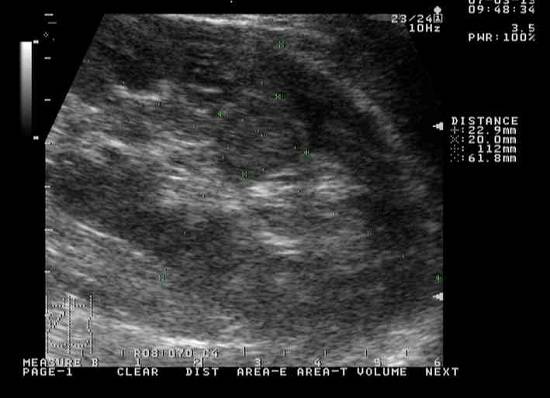

Самым распространенным диагностическим методом исследования, при помощи которого диагностируют почечные проблемы, в том числе определяют, что уже подверглась негативному воздействию паренхима, образовалась синусная киста правой почки или левой, является ультразвуковое исследование.

Ультразвуковая аппаратура позволяет выявить кисты синусные почек, достигшие в размере 3 или более миллиметров.

Однако УЗИ является не единственным способом диагностики. Наряду с ним существуют и другие эффективные способы инструментальной диагностики, к которым относятся компьютерная томография, МРТ, урография.

При помощи такой инструментальной диагностики удается оценить работоспособность почек, установить наличие патологий, степень поражения органа.

Крошечные кисты, размеры которых равны 1 мм, отлично диагностируются при проведении томографии.

В то же время максимальной эффективностью для выявления синусной кисты почек является урография, предполагающая введение в вену специального контрастного вещества.